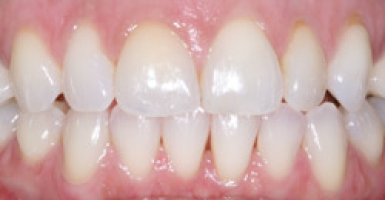

Before

After